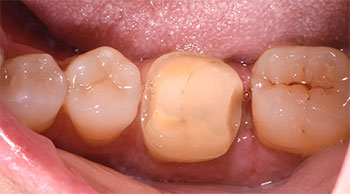

Il paziente, un uomo di 62 anni, si presentava alla nostra attenzione lamentando la frattura di un vecchio restauro in corrispondenza dell’elemento 4.6.

Tale valutazione delineava una frattura parziale della porzione occluso-distale dell’elemento 4.6 sottoposto anni prima ad un trattamento endodontico.

L’esecuzione di una radiografia endorale periapicale mostrava inoltre come tale frattura interessasse il tessuto d’attacco sovracrestale terminando 1 mm sottocresta.

Nell’ottica di una odontoiatria minimamente invasiva, si decideva dunque di eseguire un allungamento di corona clinica al fine di ristabilire una corretta connessione tra margine restaurativo ed ampiezza biologica e procedere dunque alla realizzazione di un overlay in disilicato di litio.